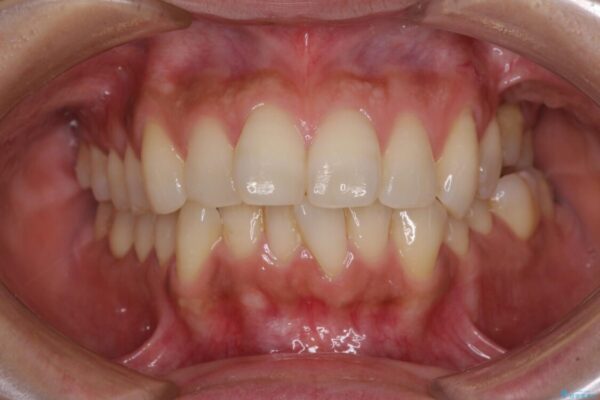

治療後について

歯の傾斜が改善され、インプラントによるクラウンが装着されたことで、物が挟まることもなくなりました。

治療後

• インビザラインによる矯正治療と奥歯のインプラント治療 治療後画像